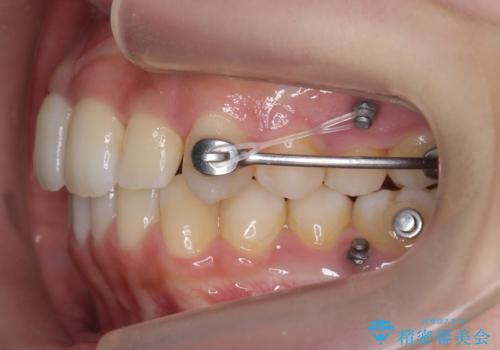

後ろに下げるために、ワイヤー矯正の前にカリエールという装置を使用しました。